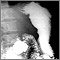

Con un método radiográfico, llamado fluoroscopia, se rastrea la forma como el bario se desplaza a través del esófago, el estómago y el intestino delgado. Se toman imágenes con usted en diferentes posiciones. Puede estar parado o sentado.

El examen se hace para determinar si usted tiene un problema estructural o funcional en el esófago, el estómago o el intestino delgado.